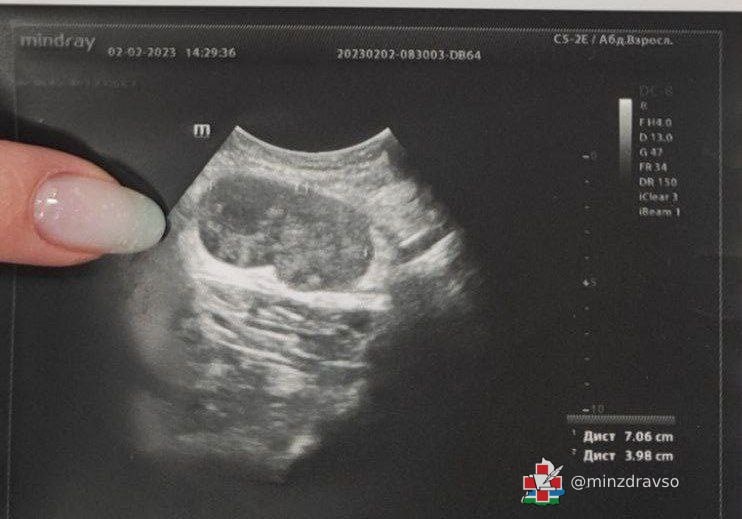

«Пациент обратился к нам с жалобами на "шарик" подмышкой. При ультразвуковом исследовании было установлено, что это увеличенный лимфоузел размером 70/40 миллиметров с изменённой структурой. Находка вызвала подозрения, пациента направили на дополнительное обследование — выполнение биопсии лимфоузла для установления точного диагноза», — рассказала врач ультразвуковой диагностики ЦГКБ №3 Жанна Краснопёрова.